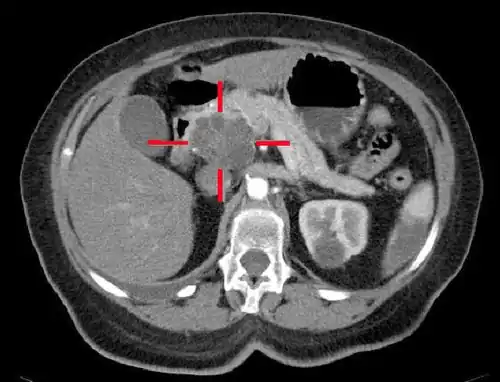

Elle vise à évaluer la taille et la localisation de la tumeur, et celles d'éventuelles métastases ganglionnaires, hépatiques, ou péritonéales.

On étudie également les rapports avec la veine porte.

Le scanner abdominal avec injection d'un produit de contraste iodé reste l'examen de référence. Il permet de mieux juger de l'extension locale et de l'existence de métastases, en particulier sur le foie et de juger ainsi de l'opérabilité[35].